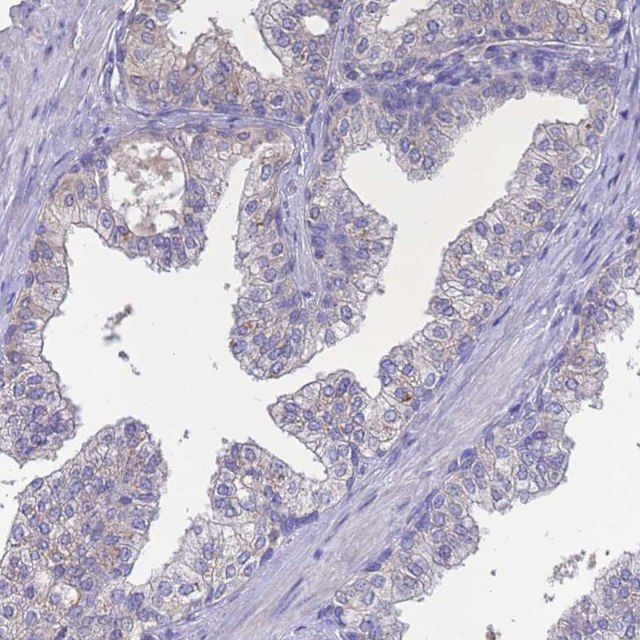

The Human Protein Atlas project can be subdivided into three efforts: Human Tissue Atlas, Cancer Atlas, and Human Cell Atlas. The antibodies that have been generated in support of the Tissue and Cancer Atlas projects have been tested by immunohistochemistry against hundreds of normal and disease tissues and through the recent efforts of the Human Cell Atlas project, many have been characterized by immunofluorescence to map the human proteome not only at the tissue level but now at the subcellular level. These images and the collection of this vast data set can be viewed on the Human Protein Atlas (HPA) site by clicking on the Image Gallery link. To view these protocols and other useful information about Prestige Antibodies and the HPA, visit sigma.com/prestige.

- IHC tissue array of 44 normal human tissues and 20 of the most common cancer type tissues.

| technique(s) | immunohistochemistry: 1:50- 1:200 |